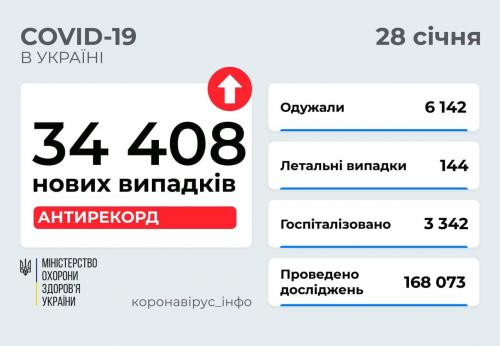

МОЗ: Уперше з початку пандемії було зроблено понад 100 тисяч ПЛР-досліджень за добу